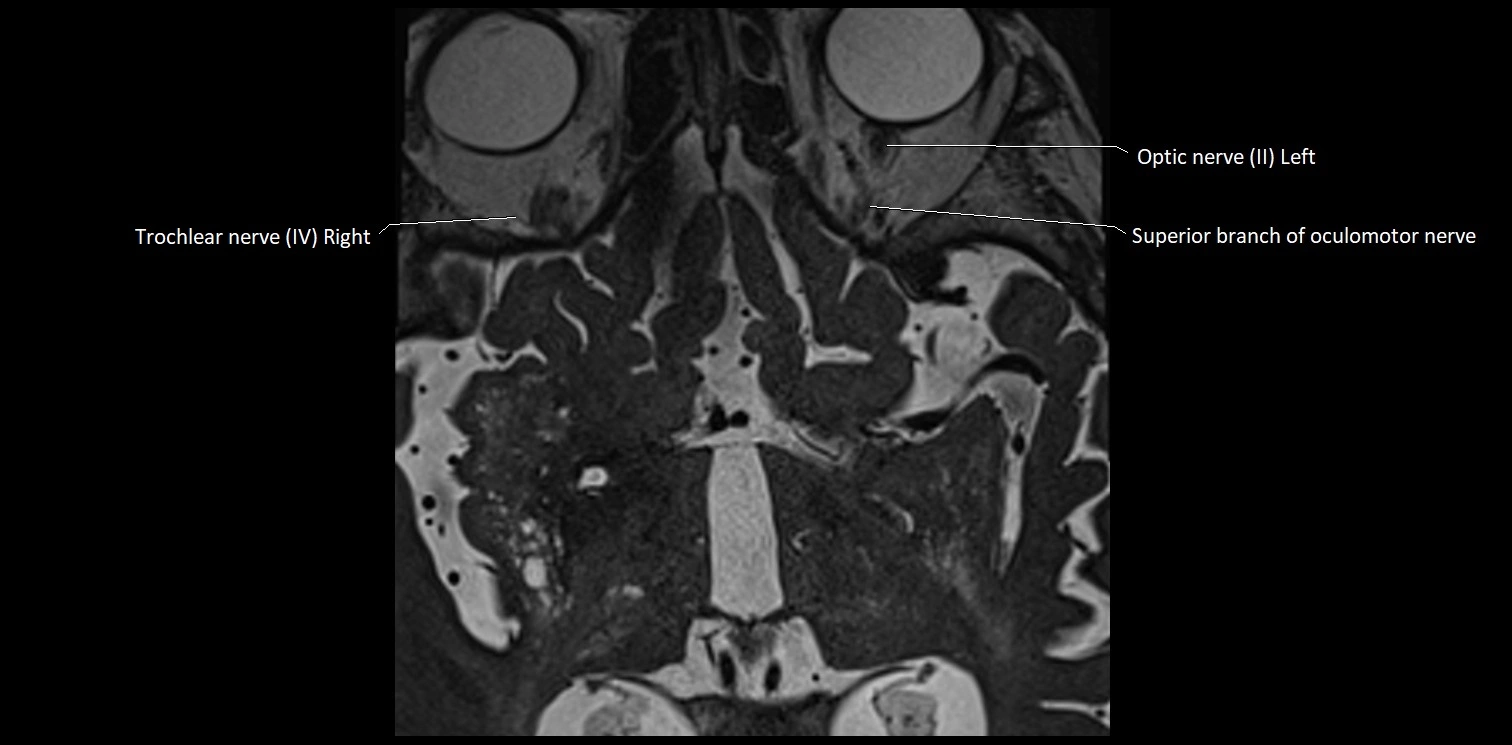

MRI images

image